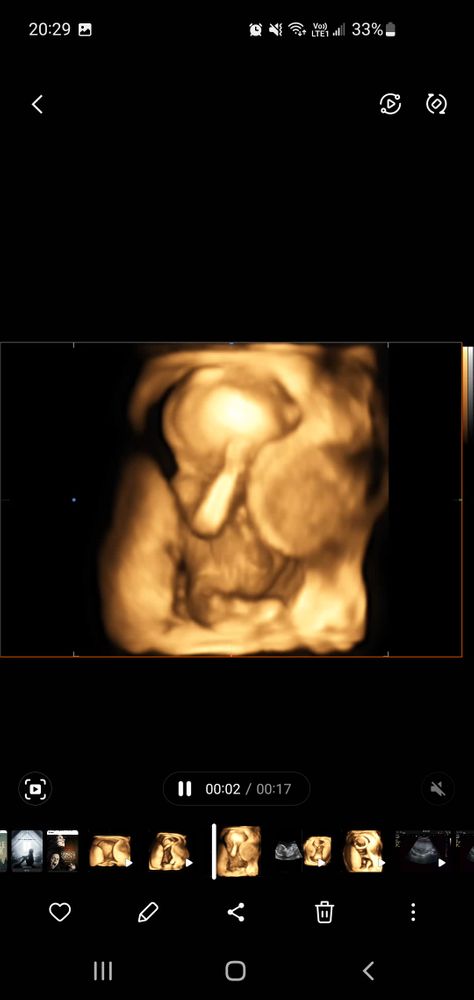

Мира, сейчас заскриню свое)

Изображение Изображение Мира,

Елена, ох точно! Вообще ничего не понятно🙈🙈

Мира, и жутко))) как будто монстрик)